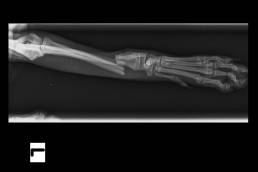

• Riduce il dolore in corso di disturbi osteo-articolari (artrosi, artriti, osteomieliti).